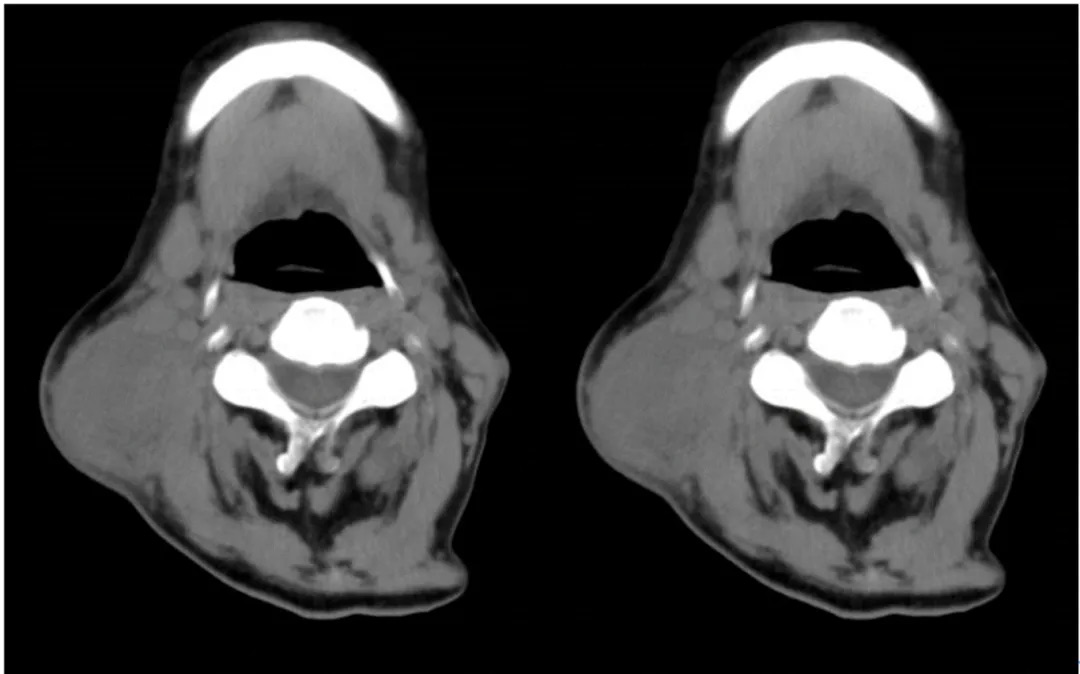

2024年1月15日PET/CT:原右颈II、III区淋巴结明显缩小,现仅示右颈血管鞘间隙呈轻度高代谢,程度近似纵隔本底(Deauville评分3分)。疗效评估为完全缓解(CR)(图1)。

图1. 影像学检查